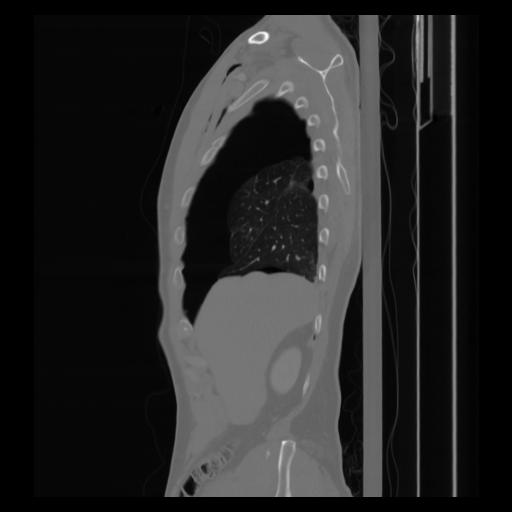

30 CUERPO,CE,Sagittal,3.000,CUERPO,Sagittal,